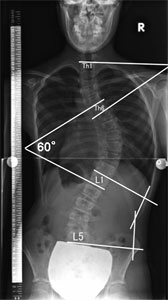

脊柱側弯症ではカーブの大きさをコブ角という角度で表します。目的とするカーブの椎体が一番傾いている椎体と椎体の間の角度を測定します。(図3)

※コブ角とは、目的とするカーブの頭側、尾側にある最大傾斜をする椎体の上縁下縁の線のなす角度。上記写真の第6胸椎と第1腰椎の間のコブ角は60度です。